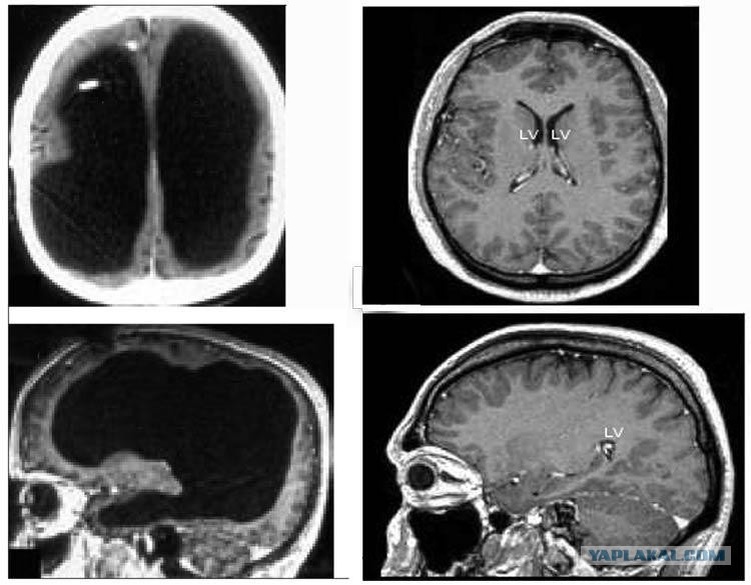

Шунт был удалён, когда ему было 14 лет. Но исследователи решили проверить состояние его мозга с помощью компьютерной томографии (КТ) и другого вида сканирования — магнитно-резонансной томографии (МРТ). Они были поражены, увидев «значительное увеличение» боковых желудочков — обычно крошечных полостей, в которых содержится спинномозговая жидкость, защищающая мозг.

Сканирование мозга мужчины показало, что огромная заполненная жидкостью полость, называемая желудочком, занимала большую часть пространства в его черепе, оставляя лишь тонкий слой мозговой ткани (см. изображение мозга пациента слева вверху).

«Мне сложно [сказать], насколько именно уменьшился мозг, поскольку мы не использовали программное обеспечение для измерения его объёма. Но визуально это более чем 50-75-процентное уменьшение», — говорит Лионель Фейе, невролог из Средиземноморского университета в Марселе, Франция.

(На картинке: справа - большое чёрное пятно показывает жидкость, которая заменила большую часть мозга пациента. Для сравнения, на изображениях справа показан обычный мозг без каких-либо отклонений.)